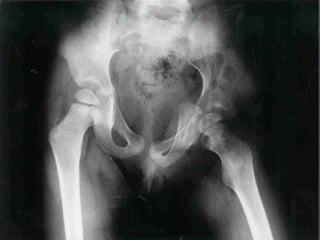

• Your pelvis helps protect the bladder,

intestines, and reproductive organs in

women.